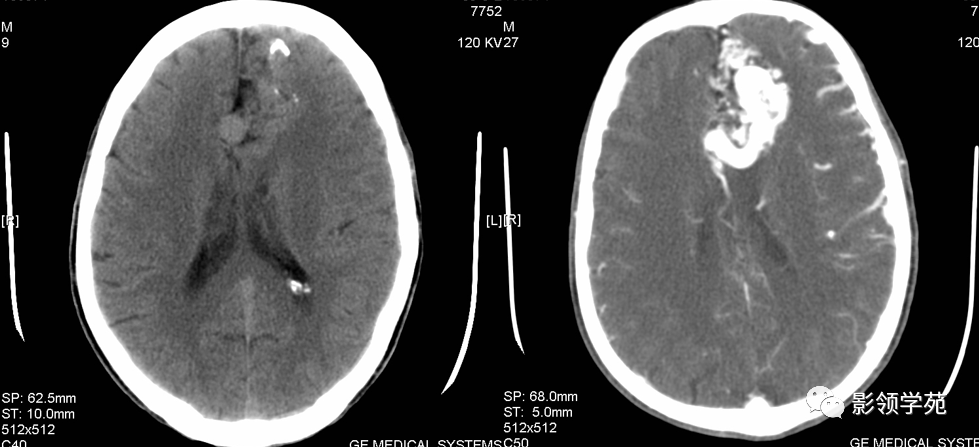

急性期CT:表现为高密度,CT值55—90Hu,可为肾形、圆形、椭圆形或不规则形,伴有周边水肿和占位效应

图片

脑出血破入脑室

CT显示急性期脑出血较MR直观